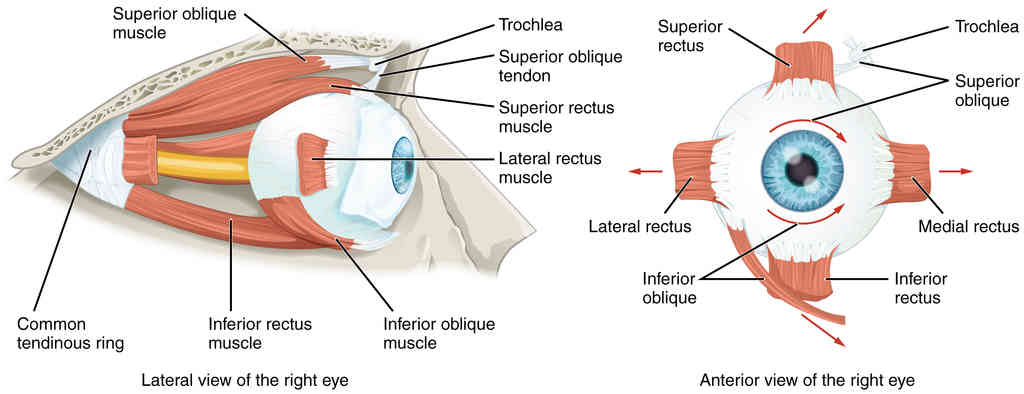

This page is under construction. For now, it is just a resource of the images found in the OpenStax Anatomy and Physiology Handbook. It wil slowly change into a revision tool. Each slide has a number. Use this to refer to the slide. When completed, it will have an unlabelled section, with labelled slides in parallel. On the unlabelled slides, write your answer and use the labelled slide to assess yourself. Keep track by also noting the number on each slide. Improvement at each attempt is important, more so than full marks on a first attempt.